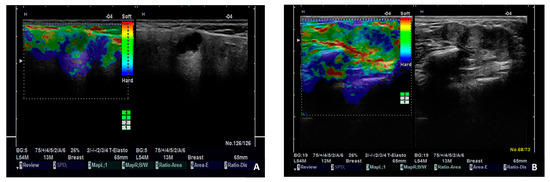

- Muntean, D.; Lenghel, M.; Ciurea, A.; Dudea, S. Viscosity Plane-wave UltraSound (ViPLUS) in the assessment of parotid and submandibular glands in healthy subjects—Preliminary results. Med. Ultrason. 2022, 24, 300–304. [Google Scholar] [CrossRef]

- Muntean, D.D.; Lenghel, M.L.; Petea-Balea, D.R.; Ciurea, A.I.; Solomon, C.; Dudea, S.M. Functional Evaluation of Major Salivary Glands Using Viscosity PLUS and 2D Shear-Wave PLUS Elastography Techniques in Healthy Subjects-A Pilot Study. Diagnostics 2022, 12, 1963. [Google Scholar] [CrossRef]